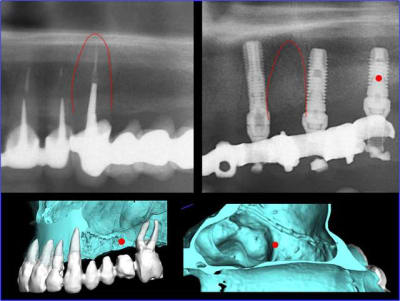

Tu trouve l’emplacement de l’implant en 26 « cocasse », sa position n’est pas choisie par hasard mais correspond au renforcement de la voute sinusienne.

1er étape le wax-Up, dans ce cas clinique il est réalisé en 3D

guide de positionnement et intrado du bridge provisoire